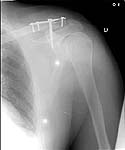

Since we have no experience with external fixation of the clavicle, we did not use this method. However, it is very interesting to see. We elected to use a T plate with a screw into the coracoid as shown in the X-ray below.

AM>We elected to use a T plate with a screw. Any comments would be appreciated.

It is a very interesting fixation but i think that the coracoid screw insertion is a little bit difficult . I have some experience in doing coraco-clavicular screw fixation and I found marked difficulty to introduce the screw.